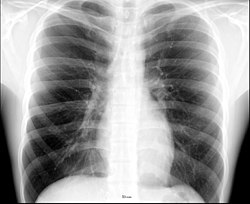

Anatomie radiographique d'une poitrine humaine.

La radioanatomie est une technique utilisée dans le domaine de l'anatomie qui repose sur l'exploitation de films radiographiques[1]. Le film radiographique représente l'image bidimensionnelle d'un objet tridimensionnel en raison de la projection de différentes structures anatomiques sur une surface plane.